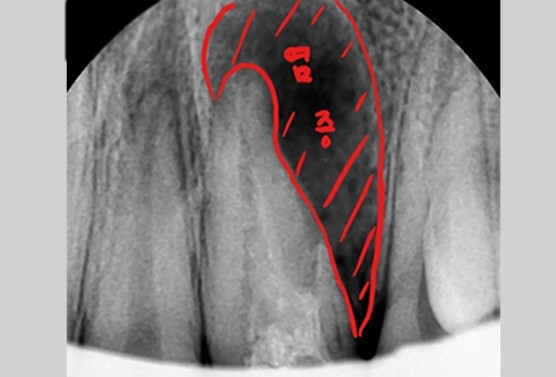

[MTA를 이용한 재신경치료와 치아천공치료]

먼저 신경관에 대한 신경치료를 시작했습니다.

신경관 부위는 실러형 MTA를 사용하고, 옆에난 구멍은 파우더형 MTA를 이용해서 막기로 합니다.

옆쪽으로 구멍이난 부위로 인해 기존 신경관 찾는게 힘들었지만 잘 찾아 들어갔네요.

그리고 이제 할 일은 소독~ 소독~ 소독~ 약재를 잘넣고 이쁘게 마무리 하였습니다.

[치료 후 2달 후의 모습]

2달 후 모습입니다.

다행히 경과가 좋아보입니다. 주변 염증부위가 사라지고 뼈가 차오르는게 보이네요.